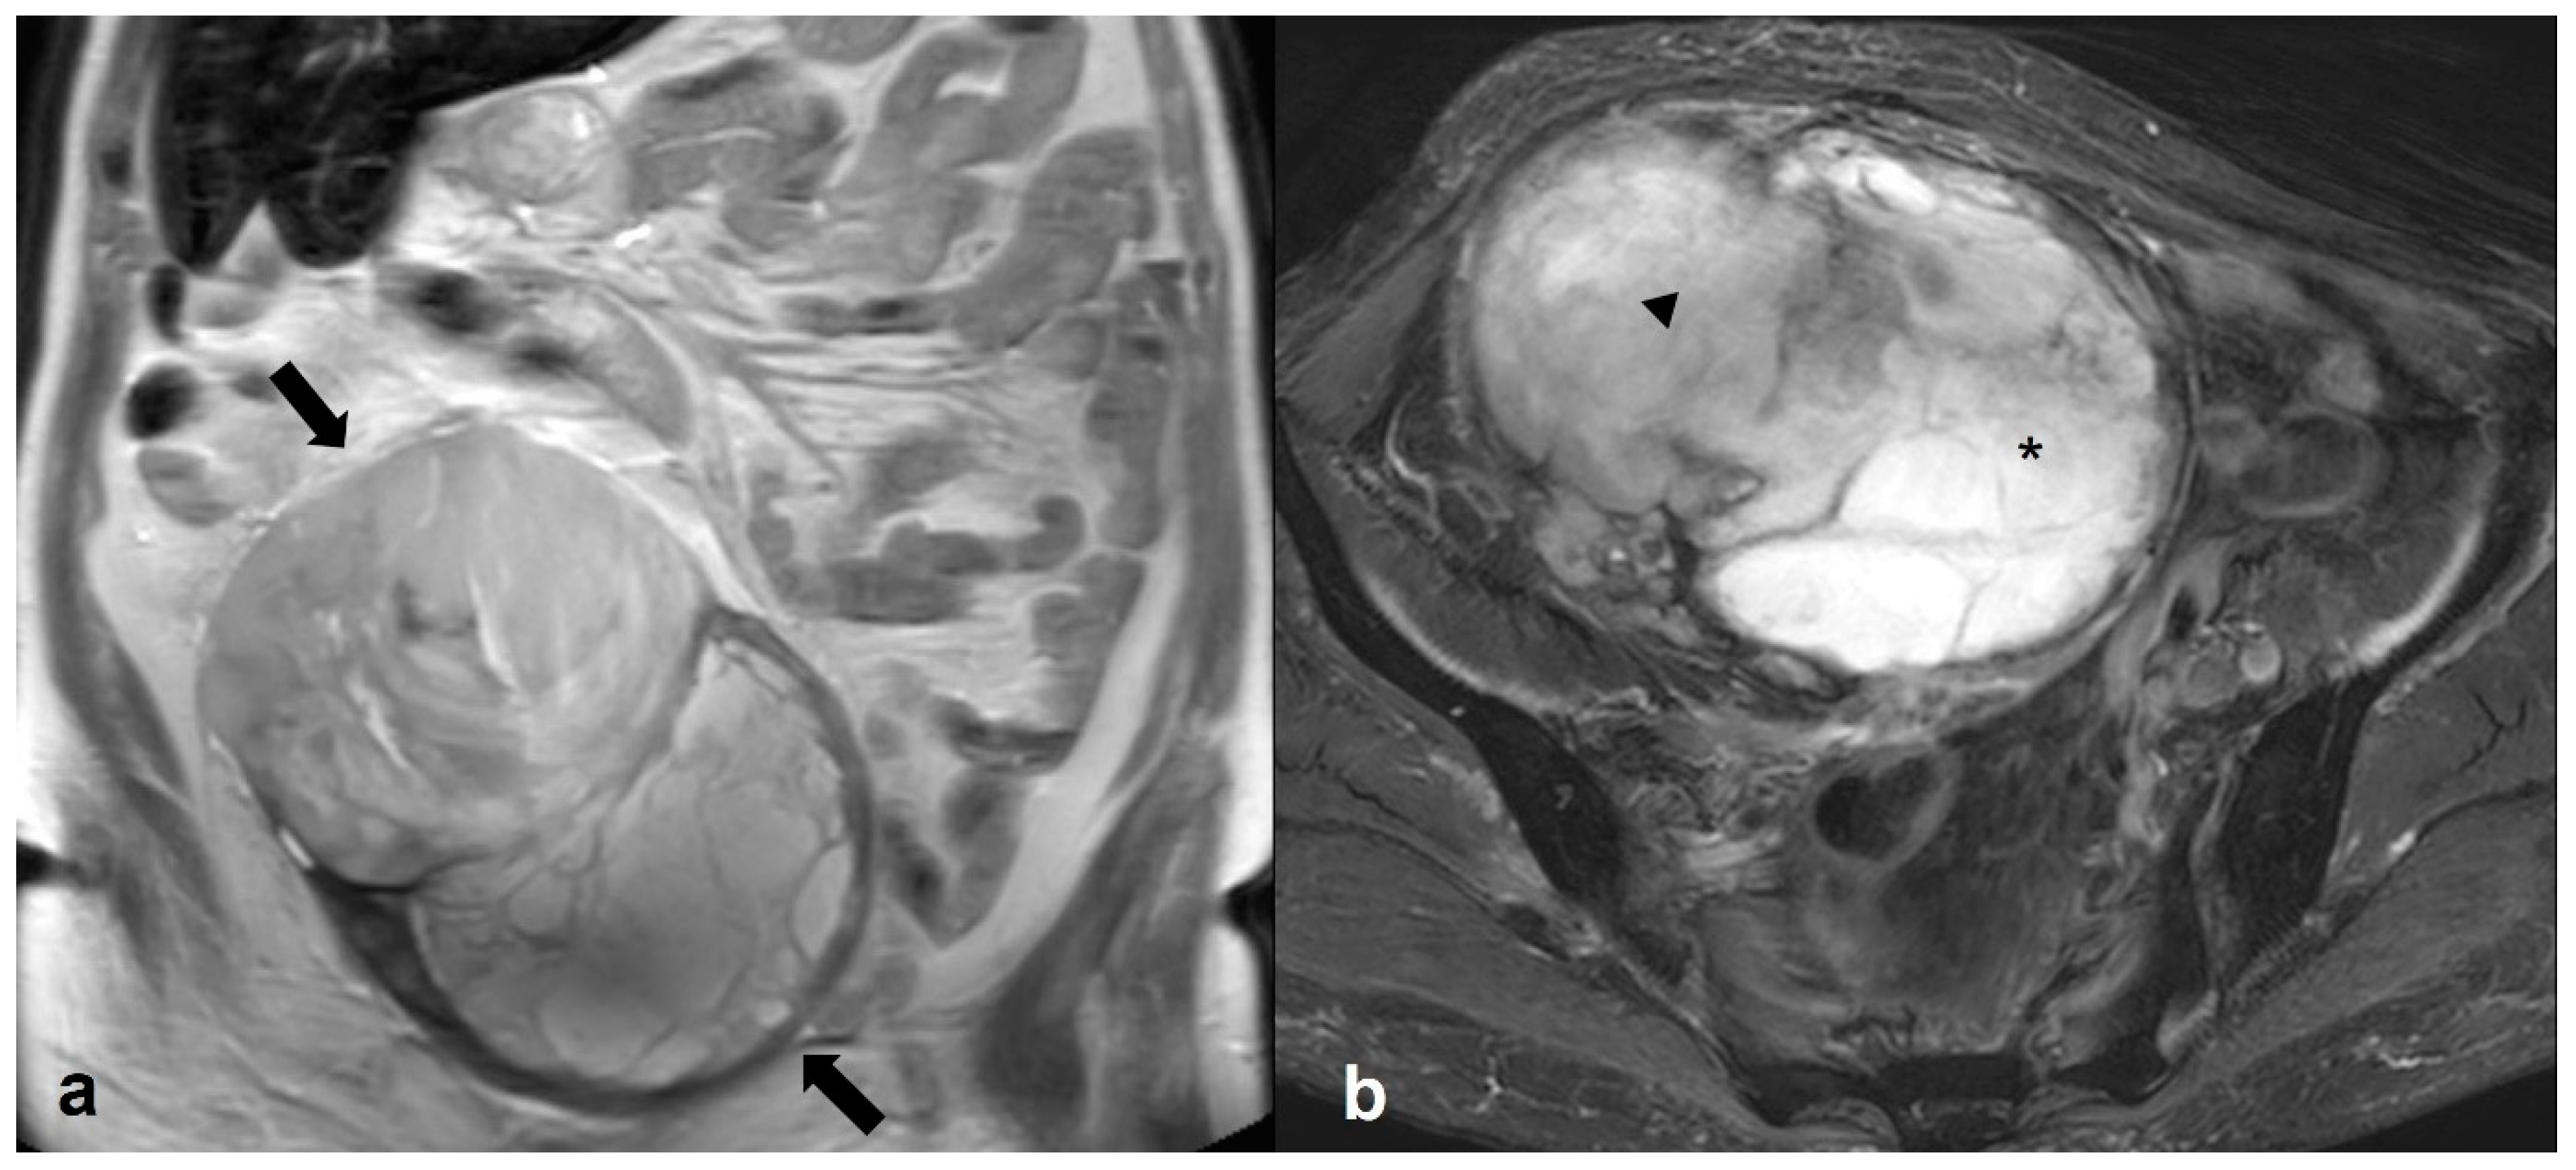

2.6.1. Mucinous Rectosigmoid Cancer

2.6.2. Appendiceal Mucocele—PMP

2.6.3. Liposarcoma/Schwannoma